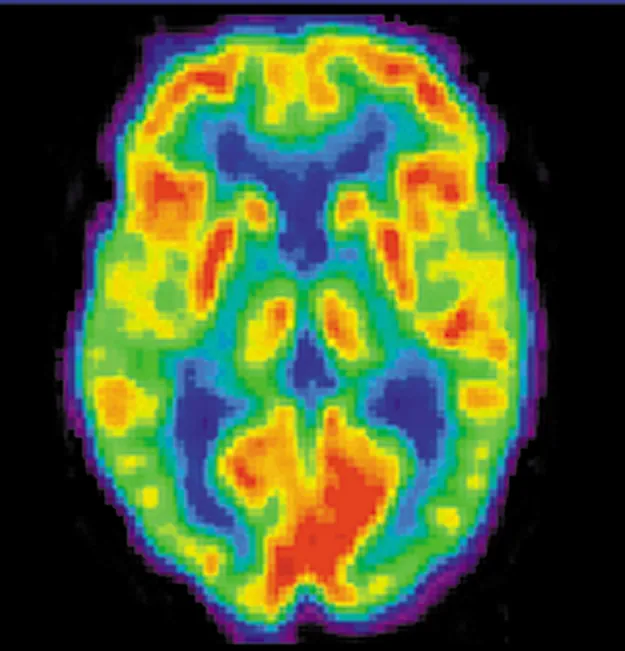

A brain scan. Different regions of the brain are shown in different colors.

Figure 32.2 A radiopharmaceutical is used to produce this brain image of a patient with Alzheimer’s disease. Certain features are computer enhanced. (credit: National Institutes of Health)